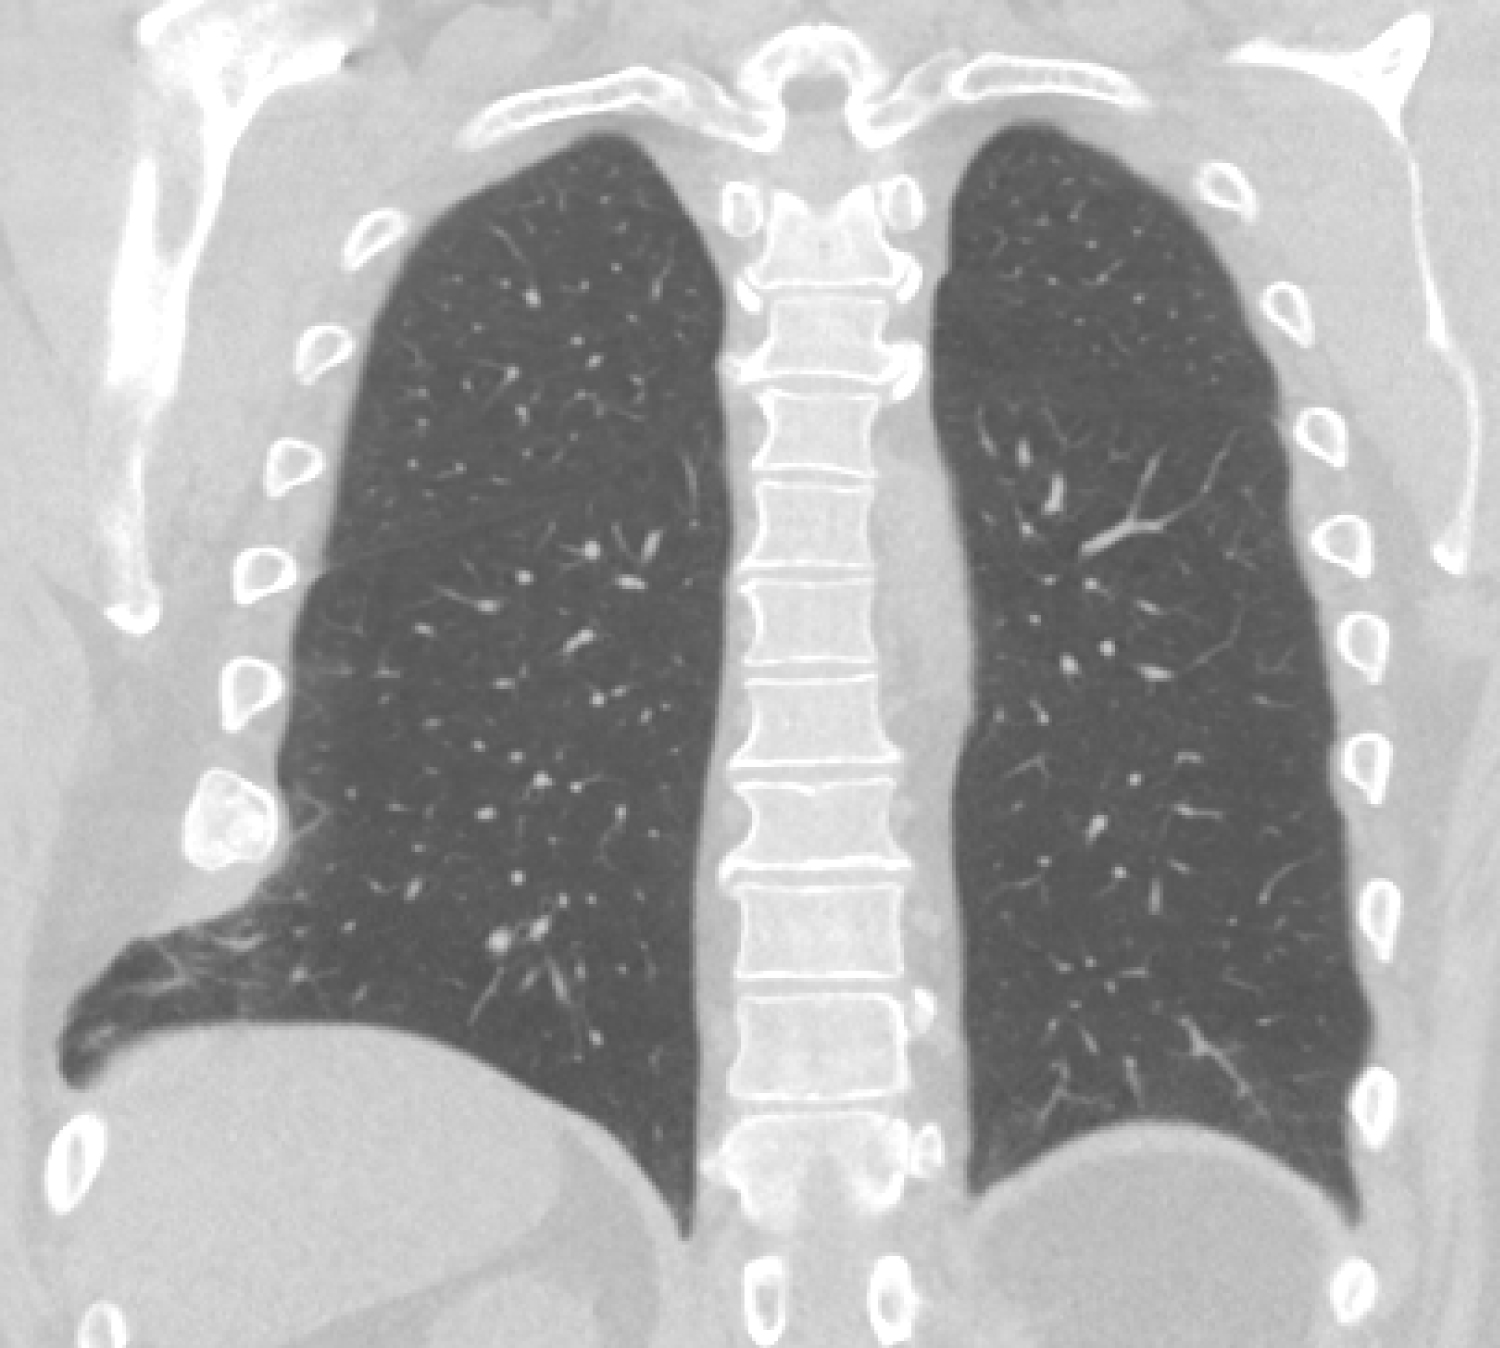

A 73-year-old male with a history of hypertension, obesity and smoking presented at the emergency room (ER) with complains of chest pain and dyspnoea. The symptoms had started earlier in the day with coaching spells without prior trauma. Plain X-ray of the chest showed no abnormalities, however a Computed Tomogram (CT) scan revealed distension of the 7th and 8th ribs on the left side with intercostal lung herniation (Figure 2). The patient was admitted to the hospital for observation and pain management. A large hematoma over the left flank developed and the patient experienced increasing respiratory distress due to pain over the next couple of days. As conservative treatment was unsuccessful the patient was planned for surgery. A left sided thoracotomy was performed showing a complete rupture of the intercostal musculature between ribs 7 and 8, accompanied by herniation of lung tissue. A polypropylene mesh was placed covering the defect as an underlay beneath the ribs and secured by sutures to the overlaying ribs. Next the ribs where approximated by vicryl sutures. Postoperatively the patient made a full recovery without major complications or disability after one year of follow up.

Figure 2: Computed tomogram frontal plane view shows herniation of lung tissue between ribs 7 and 8 on the left side. View Figure 2